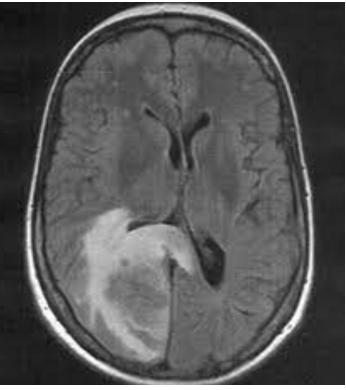

However, there has been some controversy over lecanemab, which is why it is still going through clinical trials before being made readily available to the public. A sixty five year old woman, with early Alzheimer’s, who was part of the clinical trial for this drug recently died due to a huge brain haemorrhage. Some researchers have linked this death to her use of lecanemab. This is the second death related to the drug which has raised lots of scepticism and many questions about its safety. Some researchers have suggested that the use of lecanemab should be strictly regulated even if it does pass clinical trials and is approved by the FDA

The woman was admitted to the emergency room after having suffered a stroke and was given a common intervention called tPA, which is a blood thinner used to destroy blood clots. However the tPA did anything but help her stroke. Instead her brain's outer layer immediately started bleeding and the woman died a few days later. After her autopsy it seemed as though the lecanemab was a large contributing factor to her death. The woman had a condition called cerebral amyloid angiopathy (CAA) which means that a plaque of beta-amyloid had built up and replaced the muscle of her blood vessel walls. As lecanemba’s job is to destroy any beta-amyloid in the brain, it severely weakened her blood vessels. Therefore it was easy for the blood vessels to burst, which is exactly what happened when she was given tPA to thin her blood. Unfortunately, the bleeding was so aggressive that it became fatal. The death of this woman has led to many arguments as to whether the benefits of lecanemab outweighs its possibly fatal consequences. And many researchers are urging the FDA to make careful considerations and be extremely cautious in their decision to allow this drug.